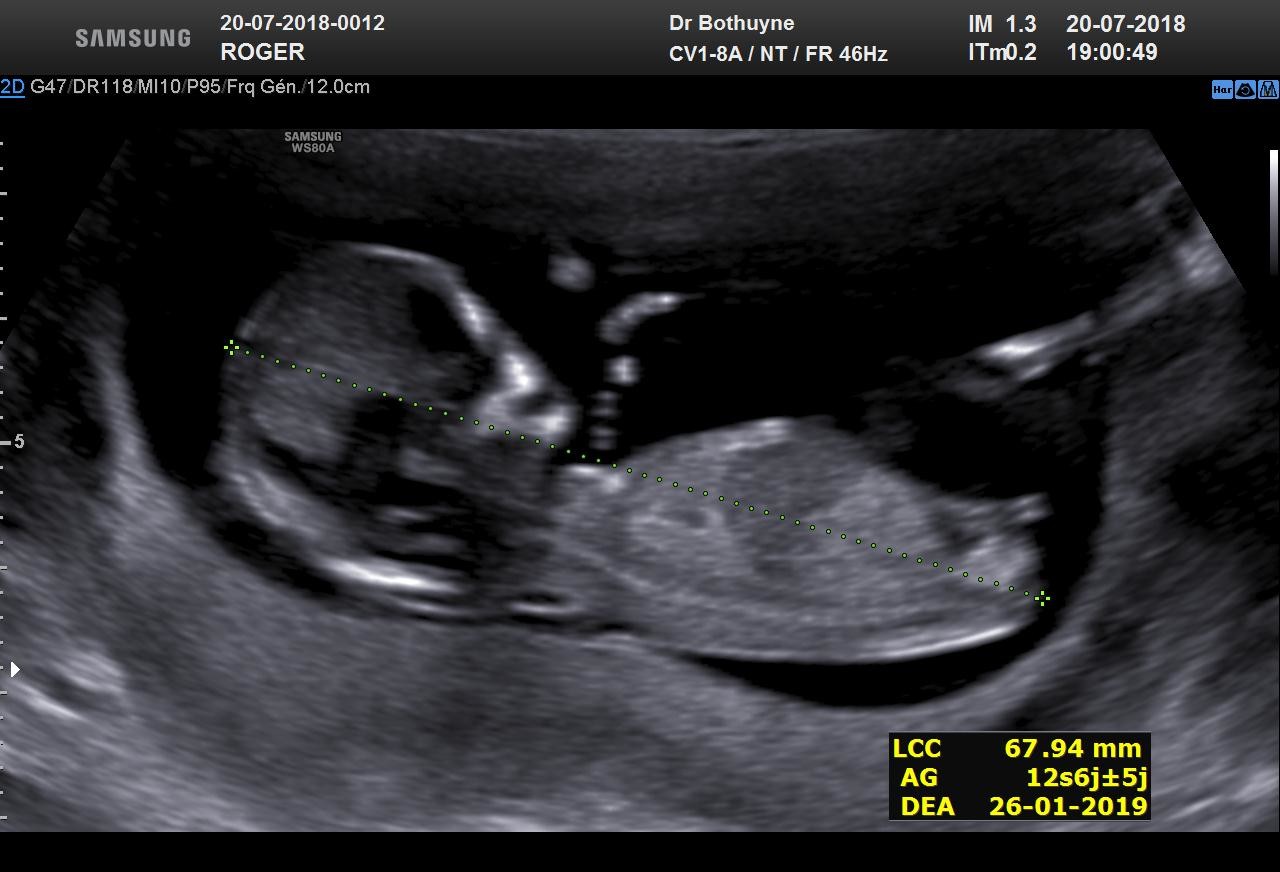

Estil possible de choisir le sexe de bébé?Echo Show 8 (1st Gen, 19 release) HD smart display with Alexa – Unlimited Cloud Photo Storage – Digital Photo Display Charcoal Amazon $ $ 109 99 (238,125)Ainsi dans de bonnes conditions techniques (échographiste entrainé, échographe performant et adapté à l'échographie de grossesse, bon passage des ultrasons à travers la paroi maternelle, bonnes positions du foetus et surout terme de grossesse supérieur à 12,5 SA), le diagnostic du sexe foetal est possible dans plus de 90 % des cas au premier trimestre

Analyser son échographie pour connaître le sexe de bébé Il vous faut donc passer l'échographie T1 (entre 11 et 13 semaines d'aménorrhée) pour avoir des éléments de réponse C'est généralement un grand moment dans votre calendrier de grossesse, émouvant pour les parents, car le fœtus commence à ressembler à un bébéLes envies peuvent également indiquer le sexe du bébé Quand on a envie de manger des produits sucrés, comme du chocolat, des biscuits, ou des bonbons, c'est une fille à l'intérieur du ventre Si l'on opte plutôt pour des frites ou n'importe quelle autre forme d'apéritif salé, c'est un garçonLa 1ère chose qu'elle nous a demandé, c'était de savoir si on voulait connaitre le sexe de cookie En France, il avait fallu qu'on demande au gynéco (un vieux monsieur un peu bourru) à la fin de l'examen pour savoir pour Mlle E lors de cette écho

Échographies Le moyen le plus fiable de connaître le sexe du bébé est l'échographie"La première échographie se déroule au cours du troisième mois de grossesse entre la 11e et la 13e semaines d'aménorrhéeDans certains cas, le sexe du bébé peutêtre annoncé lors de ce premier examen", explique le Dr Philippe Mironneau, gynécologue etCe matin, nous avons fait notre deuxième échographie Ce matin, après avoir un peu stressé parce que la sagefemme ne disait rien en regardant ce petit cœur battre, elle nous a rassuré en nous disant que tout allait bien pour ce beau bébé de 500 g, qui avait bien poussé Ce matin, nous avons appris qu'une petite fille viendraitRevelation du sexe de bebe , on attend c'est le grand jour, on connait enfin qui se cache dans mon ventreNous sommes des futurs parents comblé♡ Abonne to